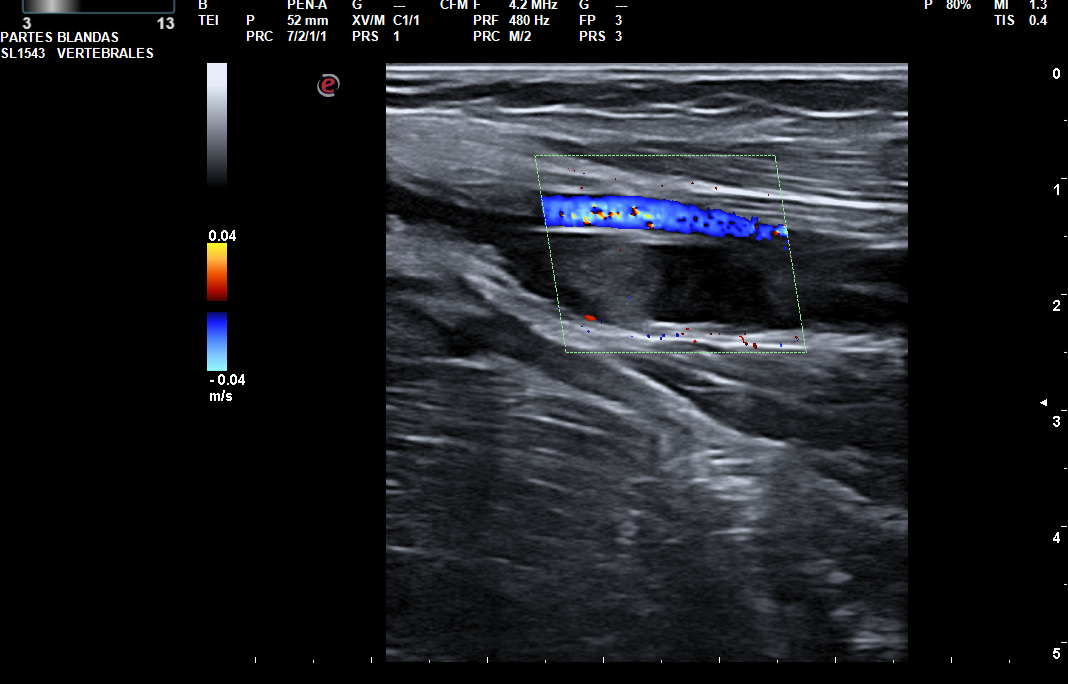

Hallazgos ecográficos

Trombo flotante en la confluencia yugulosubclavia. Ocupación por material hipoecogénico sugerente de trombosis venosa aguda, de la vena subclavia y ramas tributarias regionales, vena axilar, confluencia entre la vena cefálica (trombosada solo en su segmento más proximal a la confluencia) y axilar, así como de las venas braquiales hasta el codo.